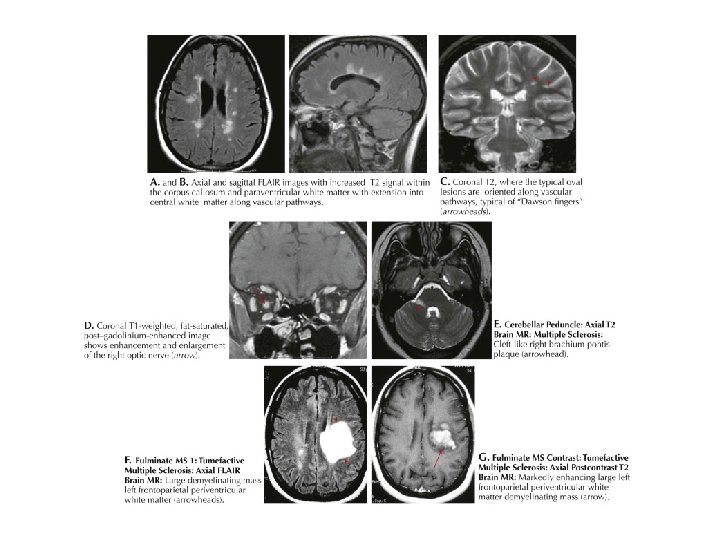

MRI BULGULARI • Periventriküler ak maddede plaklar • Serebellum / beyinsapı / servikal ve torakal spinal kord • Kontrast madde (Gadolinium) tutulumu aktif lezyon varlığını gösterir – Her zaman hastalık aktivitesinde artış ile korelasyon göstermez

MRI • MRI anormalliği: – Kesin MS’de %90 – Olası MS’de % 70

SEREBELLUMDA PLAKLAR

OPTİK SİNİR TUTULUMU

AK MADDE LEZYONLARI